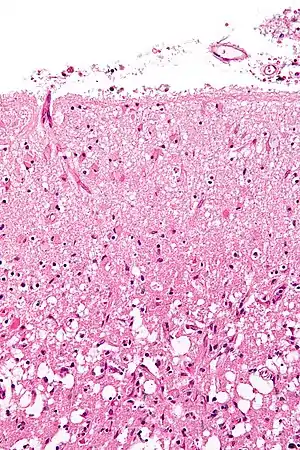

Astrogliosis (also known as astrocytosis or referred to as reactive astrogliosis) is an abnormal increase in the number of astrocytes due to the destruction of nearby neurons from central nervous system (CNS) trauma, infection, ischemia, stroke, autoimmune responses or neurodegenerative disease. In healthy neural tissue, astrocytes play critical roles in energy provision, regulation of blood flow, homeostasis of extracellular fluid, homeostasis of ions and transmitters, regulation of synapse function and synaptic remodeling.[1][2] Astrogliosis changes the molecular expression and morphology of astrocytes, in response to infection for example, in severe cases causing glial scar formation that may inhibit axon regeneration.[3][4]

Reactive astrogliosis is a spectrum of changes in astrocytes that occur in response to all forms of CNS injury and disease. Changes due to reactive astrogliosis vary with the severity of the CNS insult along a graduated continuum of progressive alterations in molecular expression, progressive cellular hypertrophy, proliferation and scar formation.[3]

Proliferating reactive scar-forming astrocytes are consistently found along borders between healthy tissues and pockets of damaged tissue and inflammatory cells. This is usually found after a rapid, locally triggered inflammatory response to acute traumatic injury in the spinal cord and brain. In its extreme form, reactive astrogliosis can lead to the appearance of newly proliferated astrocytes and scar formation in response to severe tissue damage or inflammation.